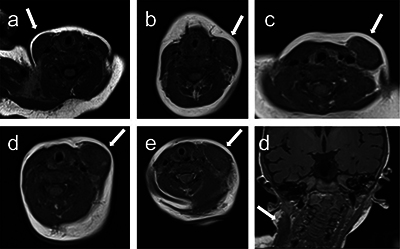

Results: We found that FC presents a T1 signal isointense to the muscle, a T2 signal hyperintense to the muscle, a variable diffusion signal and a thick enhancing peripheral ring after contrast administration.

Abstract Image